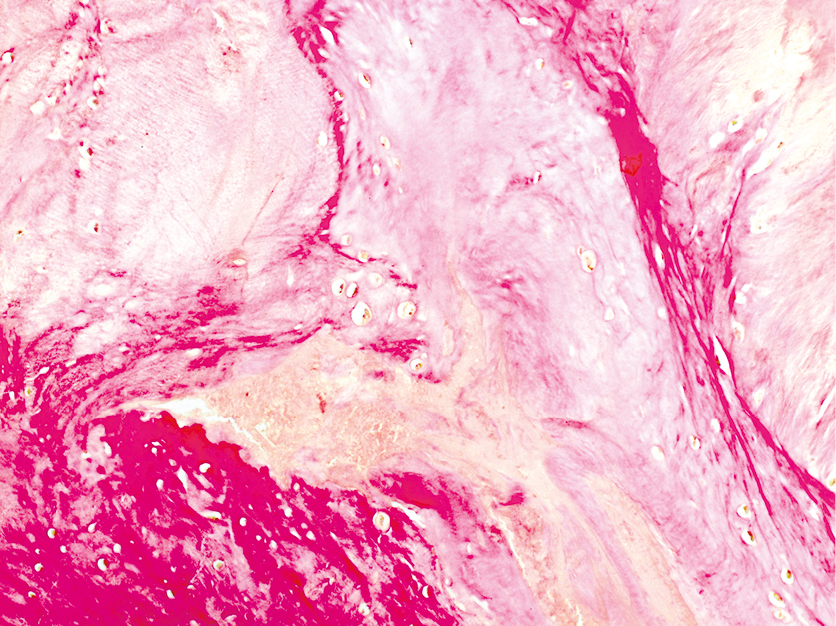

Прижизненное патологоанатомическое исследование от 23.03.2021: морфологическая картина хронического ахиллобурсита, вероятно, вследствие алкаптонурии (рис. 4–6).

Рис. 5. Беспорядочно расположенные коллагеновые волокна и бесструктурные участки в ахилловом сухожилии. Окраска пикрофуксином по Ван Гизону, ув. × 200

Fig. 5. Randomly arranged collagen fibers and structureless areas in the Achilles tendon. Picrofuchsin staining by van Gieson, × 200 magnification